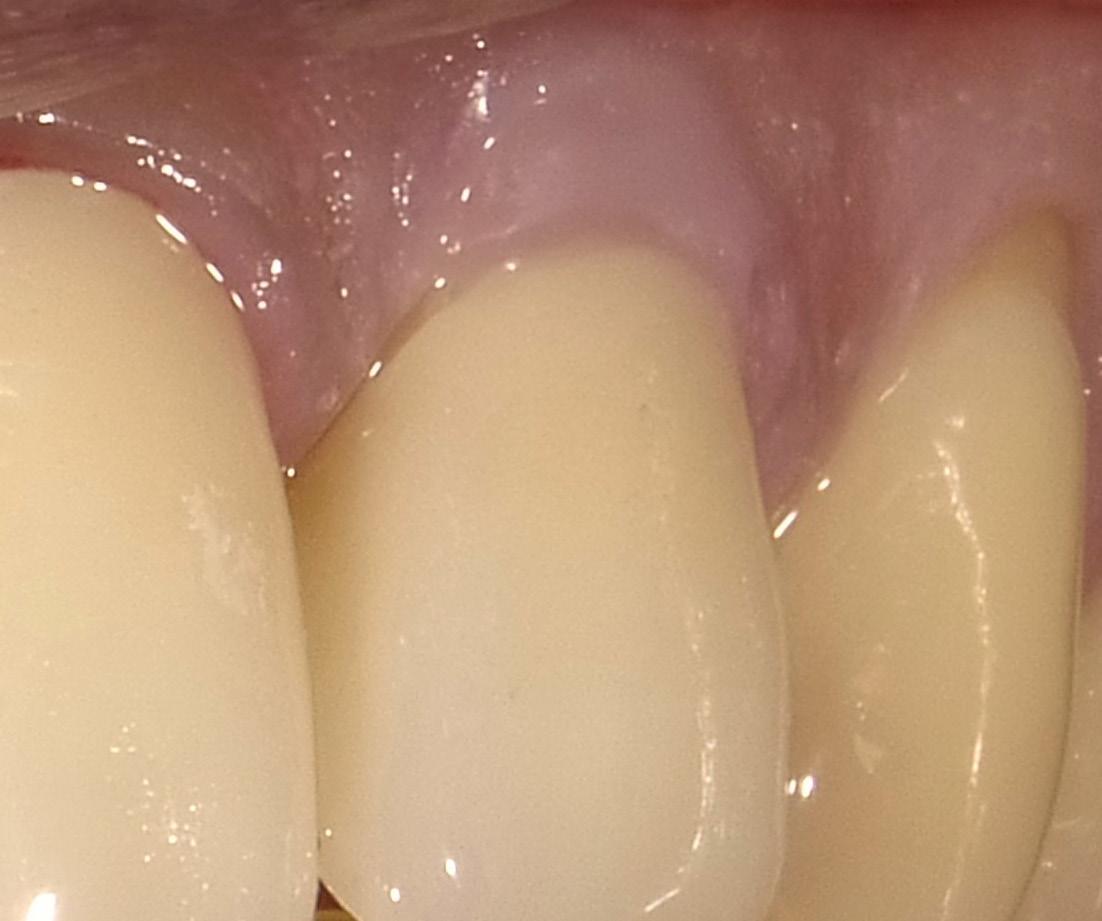

The data is clear; porcelain and composite resin are both biocompatible at the gingival margin and well tolerated.1-3 The caveat is that composite tends to cause tissue irritation if it intimate directly impinges on the gingiva.4-6 This ultimately causes unesthetic gingival recession.

Porcelain is less problematic, but marginal plaque build-up, activated by the thin layer of resin cement, leads to a similar free gingival irritation and, eventually, recession.7, 8

Even skillful subgingival margin placement will typically, within 3-5 years, due to aging, gingival irritation, or lack of home maintenance on the patient’s part, lead to unesthetic recession and full visible exposure of the darker dentinal tissue.9, 10

Thus, the restorative conclusion is to locate composite margins supragingivally,3, 11 with the resin material reasonably away (0.250.50mm) from soft periodontal structures and thereby unlikely to cause tissue irritation.

A substantial increase in the apparent length of a tooth, specifically in the anterior labial region, detracts from the esthetic smile. When restoring a Class V decay or abfraction, or perhaps a small gingival recession, an enamel-colored resin is commonly placed at the labial DEJ. Increasing the maxillary central incisor’s vertical aspect (Fig. 1) by a mere 3mm adds 30% to the apparent vertical dimension, significantly altering the cervico-incisal to

mesio-distal (CI:MD) ratio, totally upsetting the esthetic parameters of the smile. (Fig. 2) In situations where there is moderate recession, the visual imbalance is even further impaired. The CI:MD ratio impact is even greater on maxillary laterals and mandibular incisors (average 9.0mm CI). Maxillary and mandibular cuspids (average 10-11mm CI) are often the teeth most affected by gingival recession, and are also highly visible both anteriorly and laterally.

Individuals who have gingival recession, abfraction and/ or decay tend to look older than they really are (long in the tooth). Covering the darker root dentin with an enamel-like resin simply makes their teeth more visible, seemingly longer, and correspondingly less esthetic.

Beautifil II Gingiva (Shofu USA, San Marcos CA) has been specifically designed for the re-balancing of pink aesthetics in the cervical areas of the dentition. (Fig. 3) Beautifil II Gingiva is indicated for wedge-shaped defects, cervical decay, the esthetic rectification of gingival recession, shielding exposed cervical areas and splinting of mobile teeth.

Another important consideration is that the gingival margin of the restorative material (whether pink or enamel in color) must be kept supragingival and slightly away from the free gingival margin.3, 4, 6

It is imperative that a restoration that is so close to the free gingival margin be placed under conditions controlled for moisture and bleeding. Rubber dam placement is impractical (target area is positioned apically) and retraction cord may physically or chemically compromise the working area. Ideally, the patient’s oral hygiene creates a healthy gingival microenvironment, with minimal pocketing and no bleeding on probing.

In most cases, however, the practitioner must modify the actual situation to increase the likelihood of clinical success. The easiest and best technique for predictable tissue sculpting is the use of the diode laser.21-23 Utilizing low power (1.0-1.5 watts), the dentist can produce an ideal, dry, clean, and blood-free working area in less than a minute.

3. Select the appropriate Beautifil II Gingiva shade (Light Pink and Violet for this patient) and apply to the receded area to restore the buccal dimension and contour of the original soft tissue. Light cure. It is important to leave a small (0.25-0.50mm) gap between the apical margin of the restorative and the free gingival margin. (Fig. 9) This space prevents gingival irritation, is easily maintainable by the patient, and is generally not visible even with closeup photographs. (All photography done with the Shofu EyeSpecial camera, (Fig. 10) Shofu USA, San Marcos CA.)